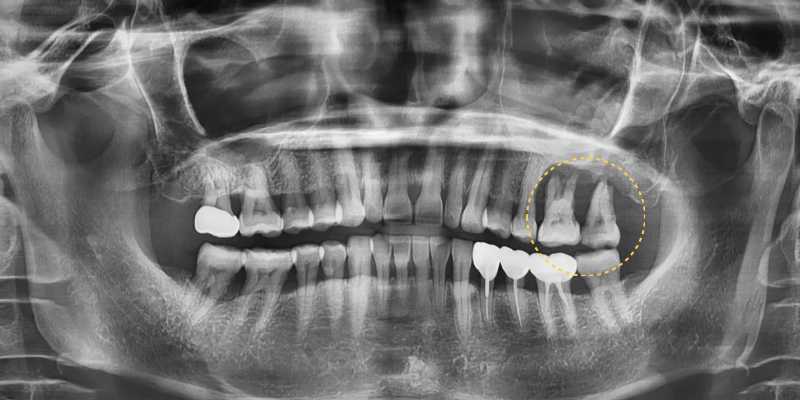

이번 증례의 환자는 50대 여성으로

지인의 소개를 통해 내원하였습니다.

기존에 다니던 치과에서는

치주염으로 인한 치조골 파괴가 심해

임플란트 식립이 어렵다는 소견을

듣고 걱정이 큰 상태였습니다.

실제 검진 결과 치주염으로 인해

어금니 부위의 치조골이

상당 부분 소실되어 있었으며

그대로 임플란트를 진행하기에는

안정성이 부족한 상황이었습니다.

이에 따라 동탄치과에서는

먼저 치조골 파괴가 심각한

치아를 발치하면서 발치와 보존술을

포함한 치조골이식술을 시행하였습니다.